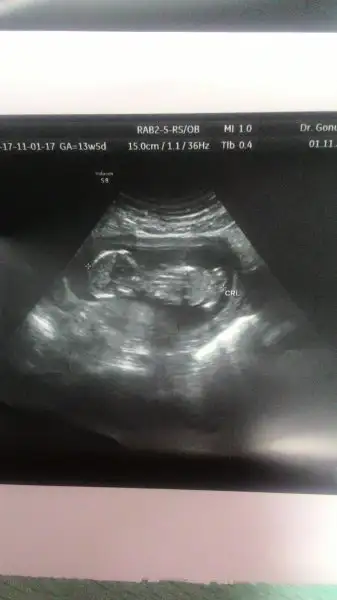

Henüz yanılmıs değilsin kesin değil dedi neye bakarak söyledi onuda sormadım valla sata göre de biraz geriden geldiği için daha 12 tamamlanmadı bende o yüzden cok emin olamadım bi dahaki randevum ay sonu bakalım orda kesinleşir inşallah önemli olan saglıklı olması o da iyi cıktı şükür ense kalınlıgı filanKız mı?? aaa yanıldımmmşaka bi yana hep diyorum genital nub muş kemik yapısıymış hepsi teori,bilimsel olarak hiçbir gerçekliği yok,12. haftadan sonra da mesane ve idrar yolu oluşumu tamamlanmaya yakın oldugu için artık iç genital organlara bakarak yorum yapıyor doktorlar da. biz eğleniyoruz sadece ama senin bir tane oğlun vardı galiba öyle hatırlıyorum ozaman yaşasın kızlaaaaaaaarrr